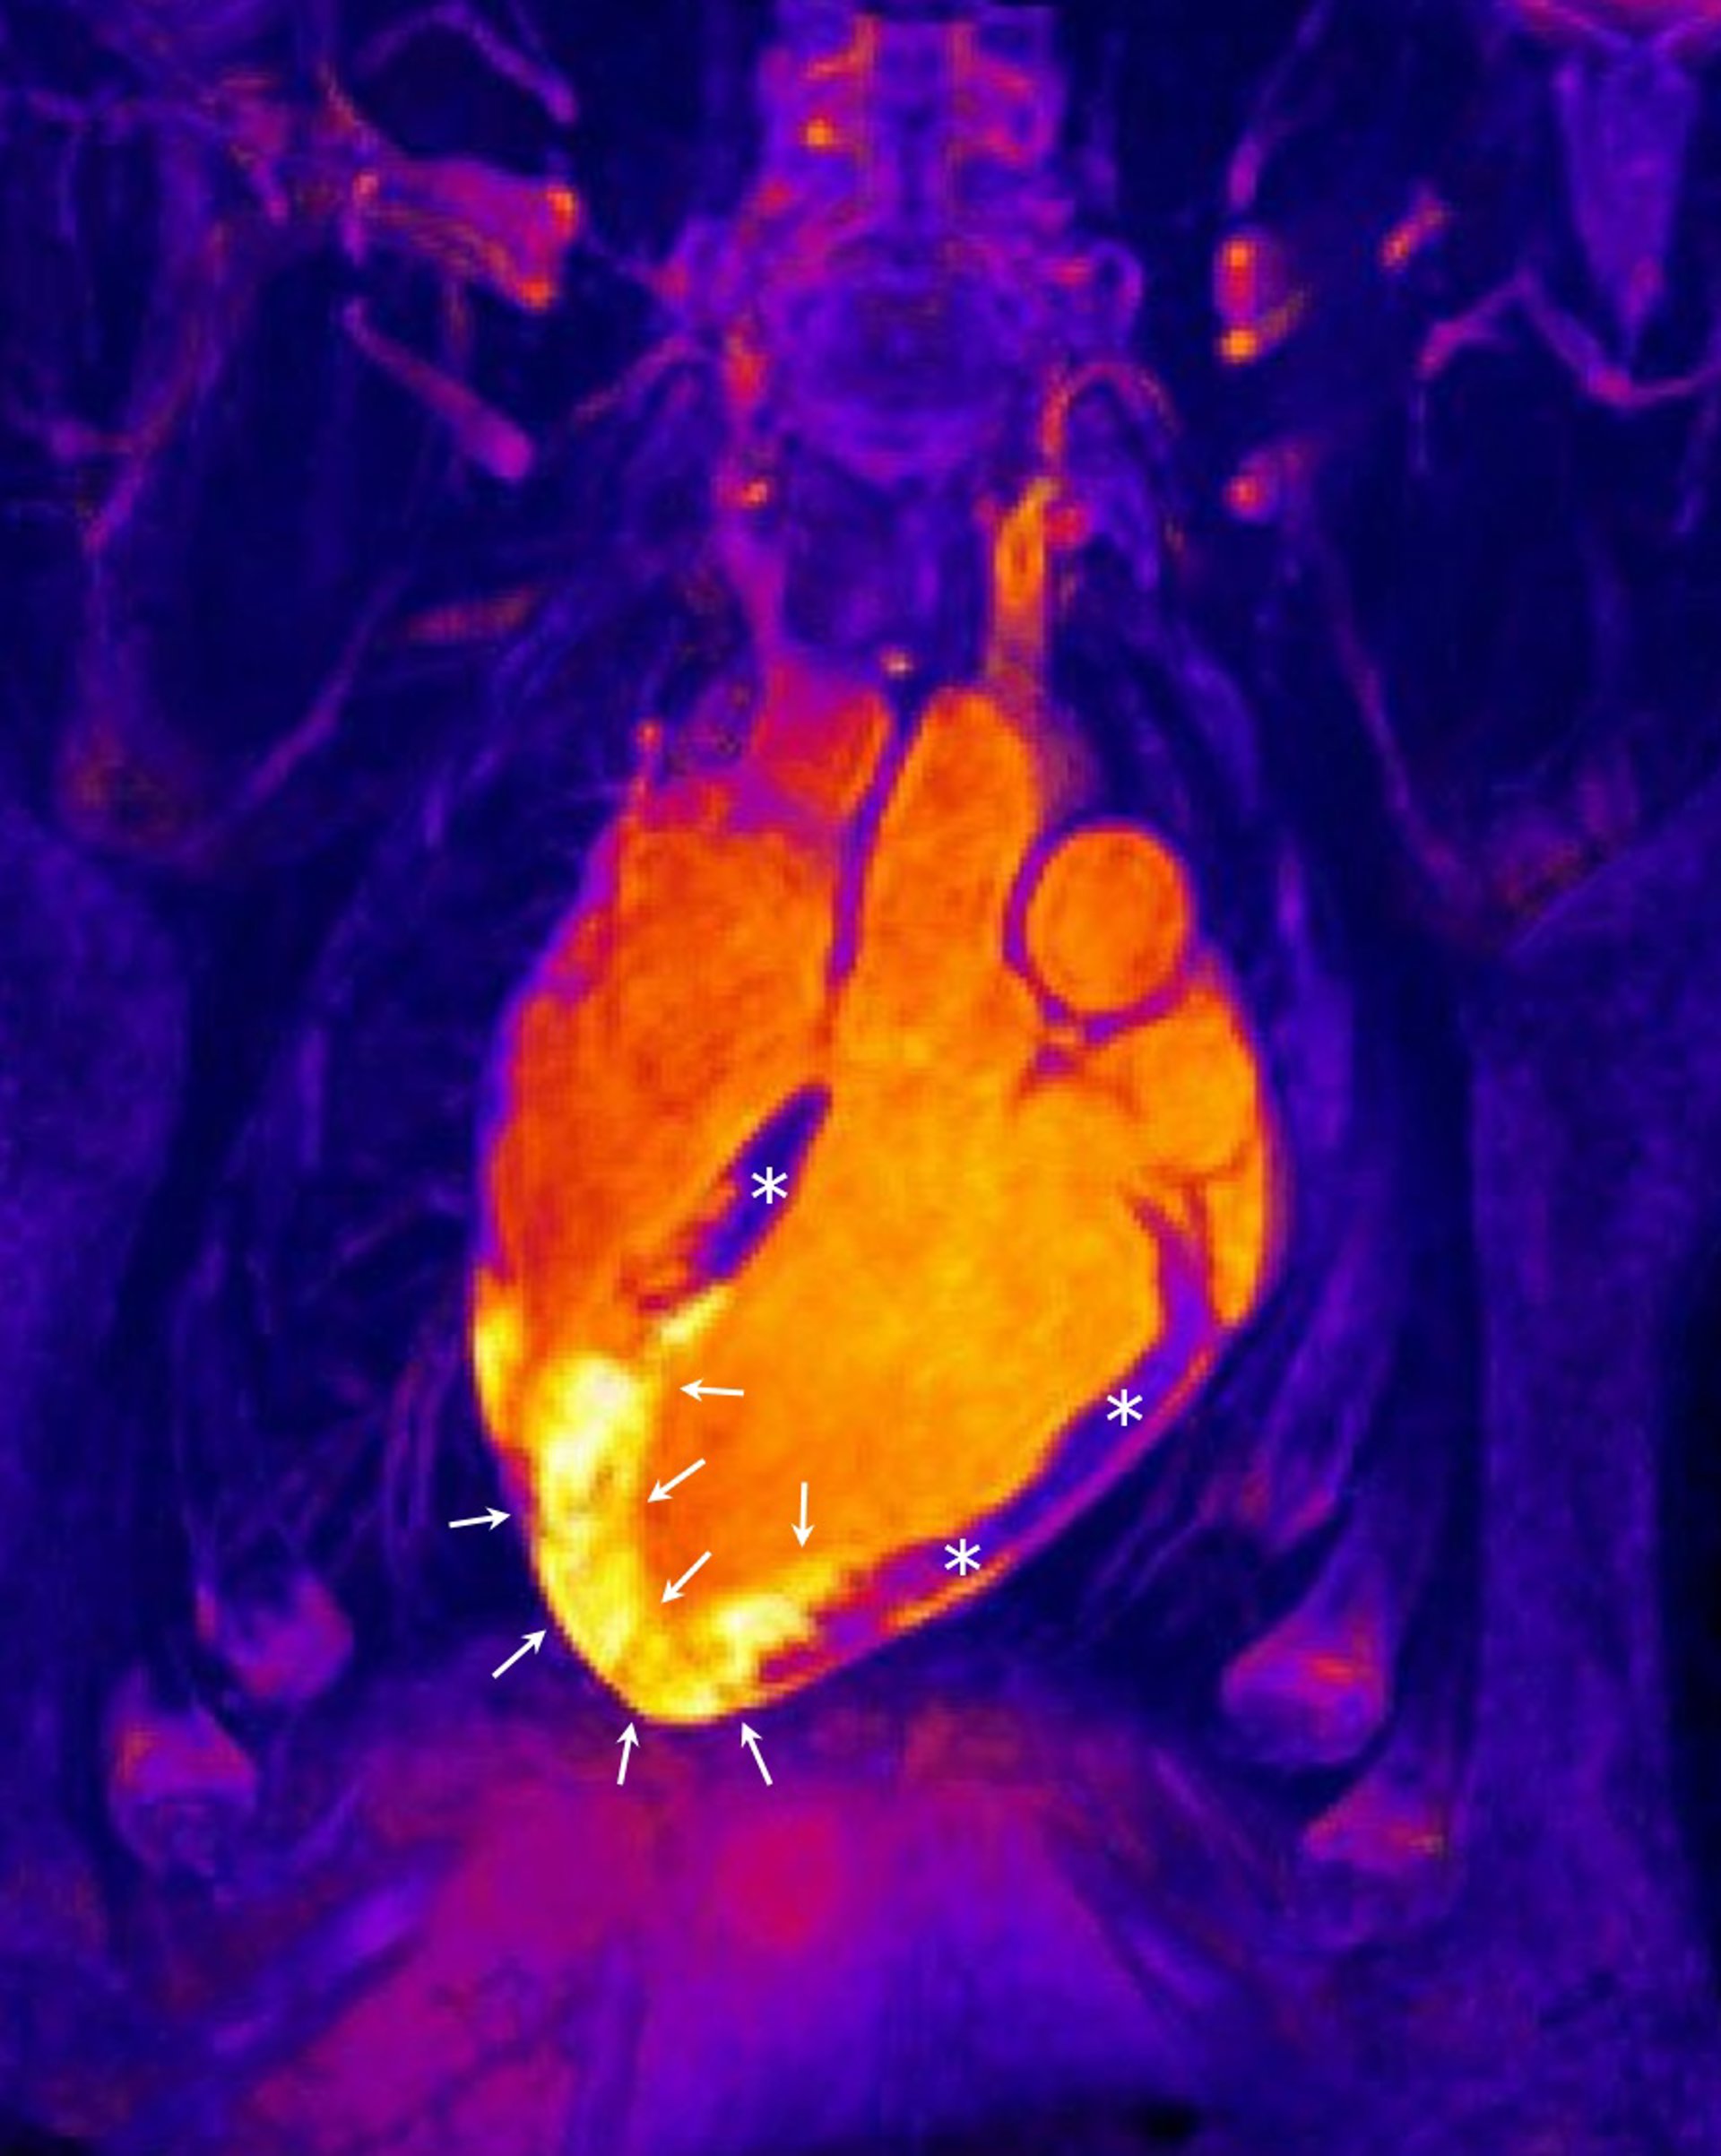

Archivo - Corazón tras un infarto agudo de miocardio

Archivo - Corazón tras un infarto agudo de miocardio - CNIC - Archivo